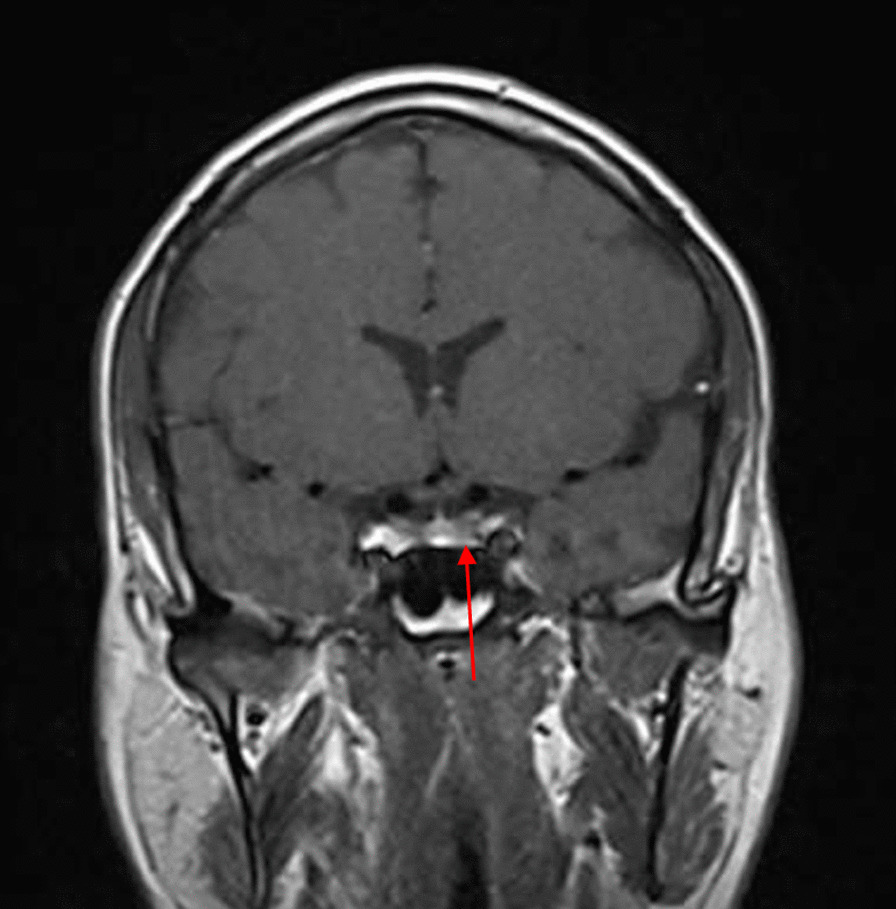

Fig. 3.

Post COVID-19 MRI findings. The image shows improvement of the pituitary microadenoma. The changes included the disappearance of the hypointense lesion and hyperintense enhancement on contrast observed on previous MRI. No macroadenoma or microadenoma is observed